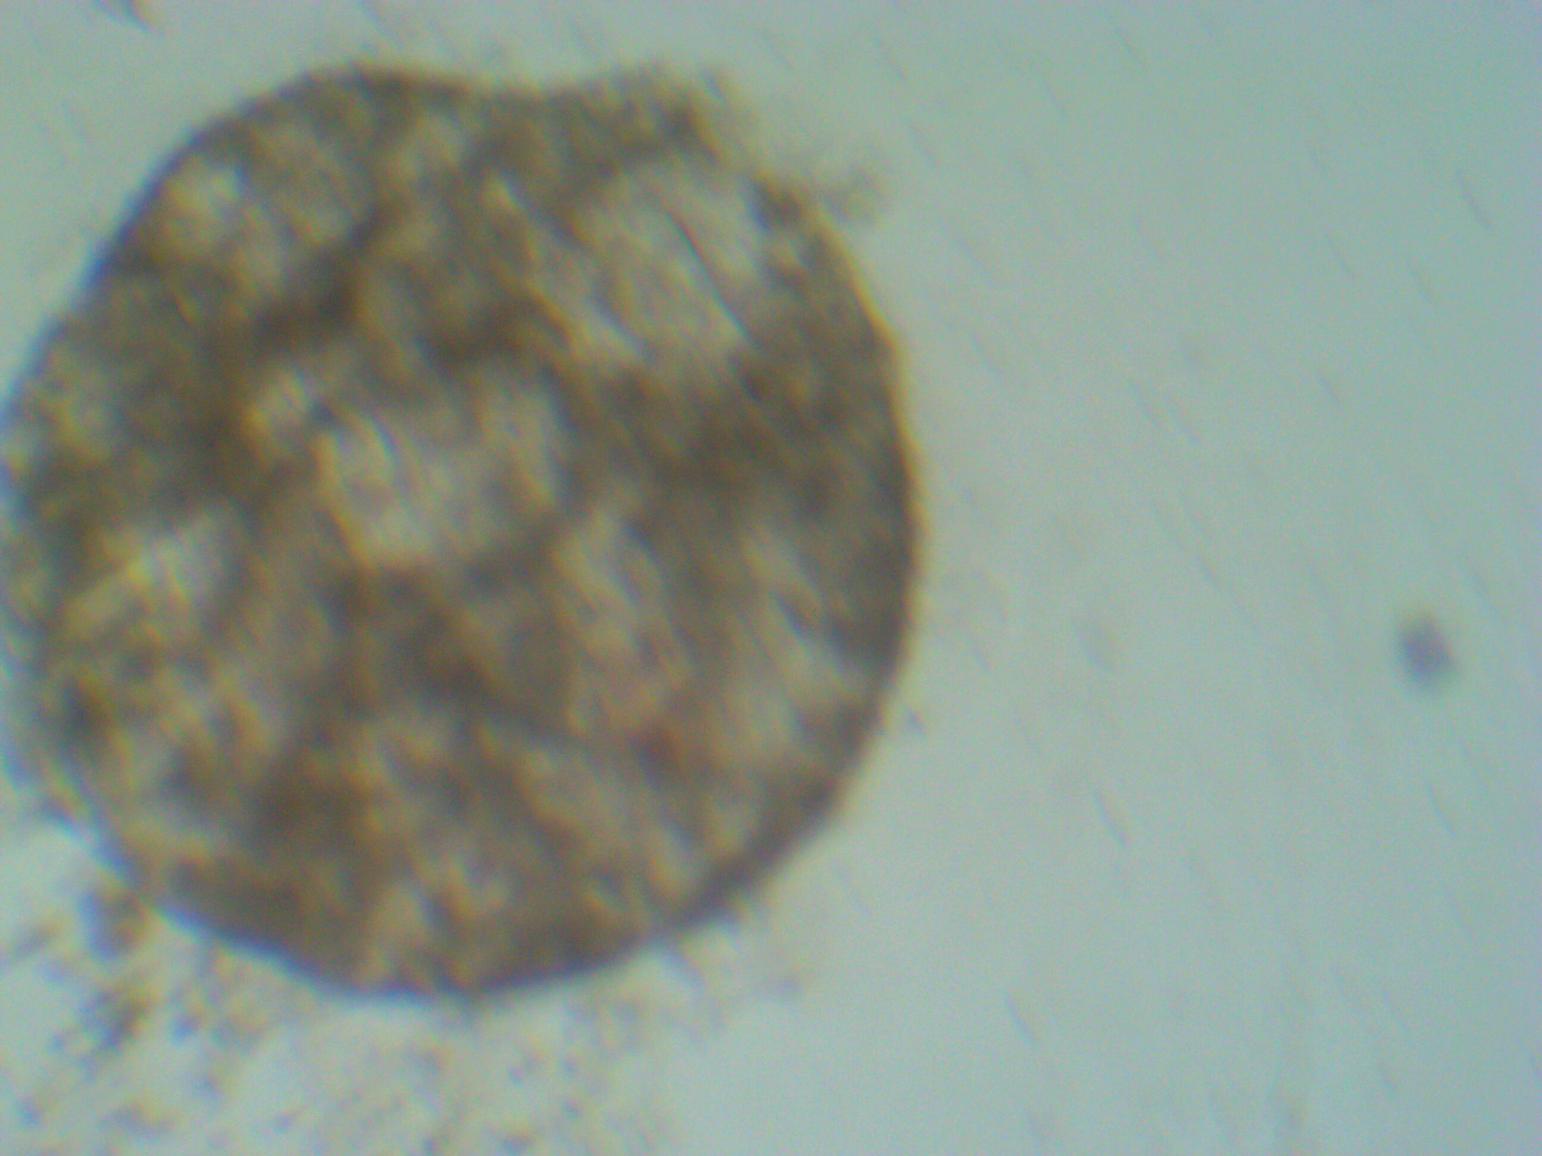

Tomorrow, we will inject 3D spheroids on the first patient and wait to see the outcome and will keep you all updated.

Respected Jahoda says in published study that, we should expect a new hair follicle/s from these injected 3D spheroidal DP cultured cells. Ofcourse i am waiting also report of versican and alkaline phosphate marker report which will conform trichogenic potential of these 3D spheroids.